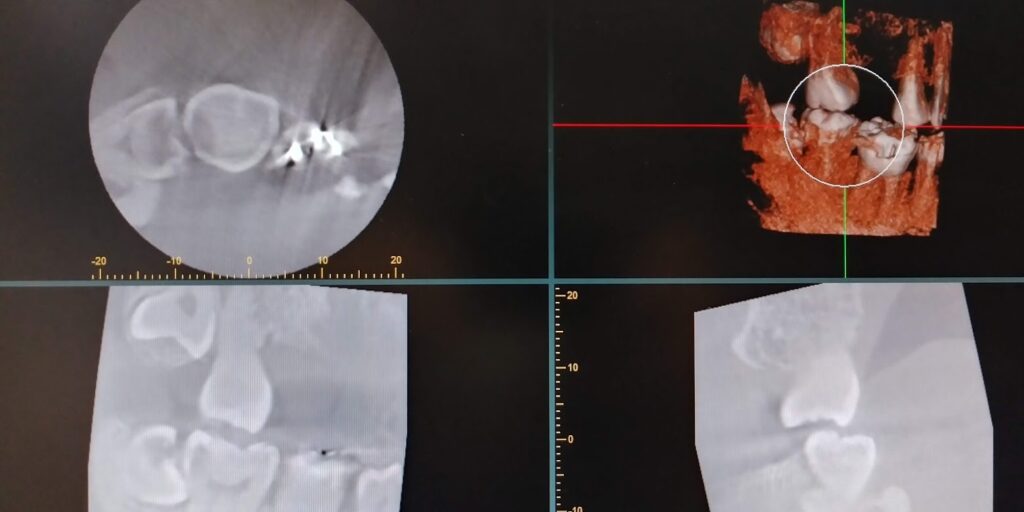

HOT ! 智歯の抜歯ナビゲ-ション 智歯の抜歯ナビゲーション - クインテッセンス出版

智歯の抜歯ナビゲ-ション 智歯の抜歯ナビゲーション - クインテッセンス出版の詳細情報

智歯の抜歯ナビゲーション - クインテッセンス出版。科学的根拠に基づいたビジュアル下顎埋伏智歯抜歯_NoLink。300-17854a.png。

智歯の抜歯ナビゲ-ション

クインテッセンス出版

笠崎安則

2003/08/08

• 智歯の抜歯ナビゲーション - クインテッセンス出版

• 科学的根拠に基づいたビジュアル下顎埋伏智歯抜歯_NoLink